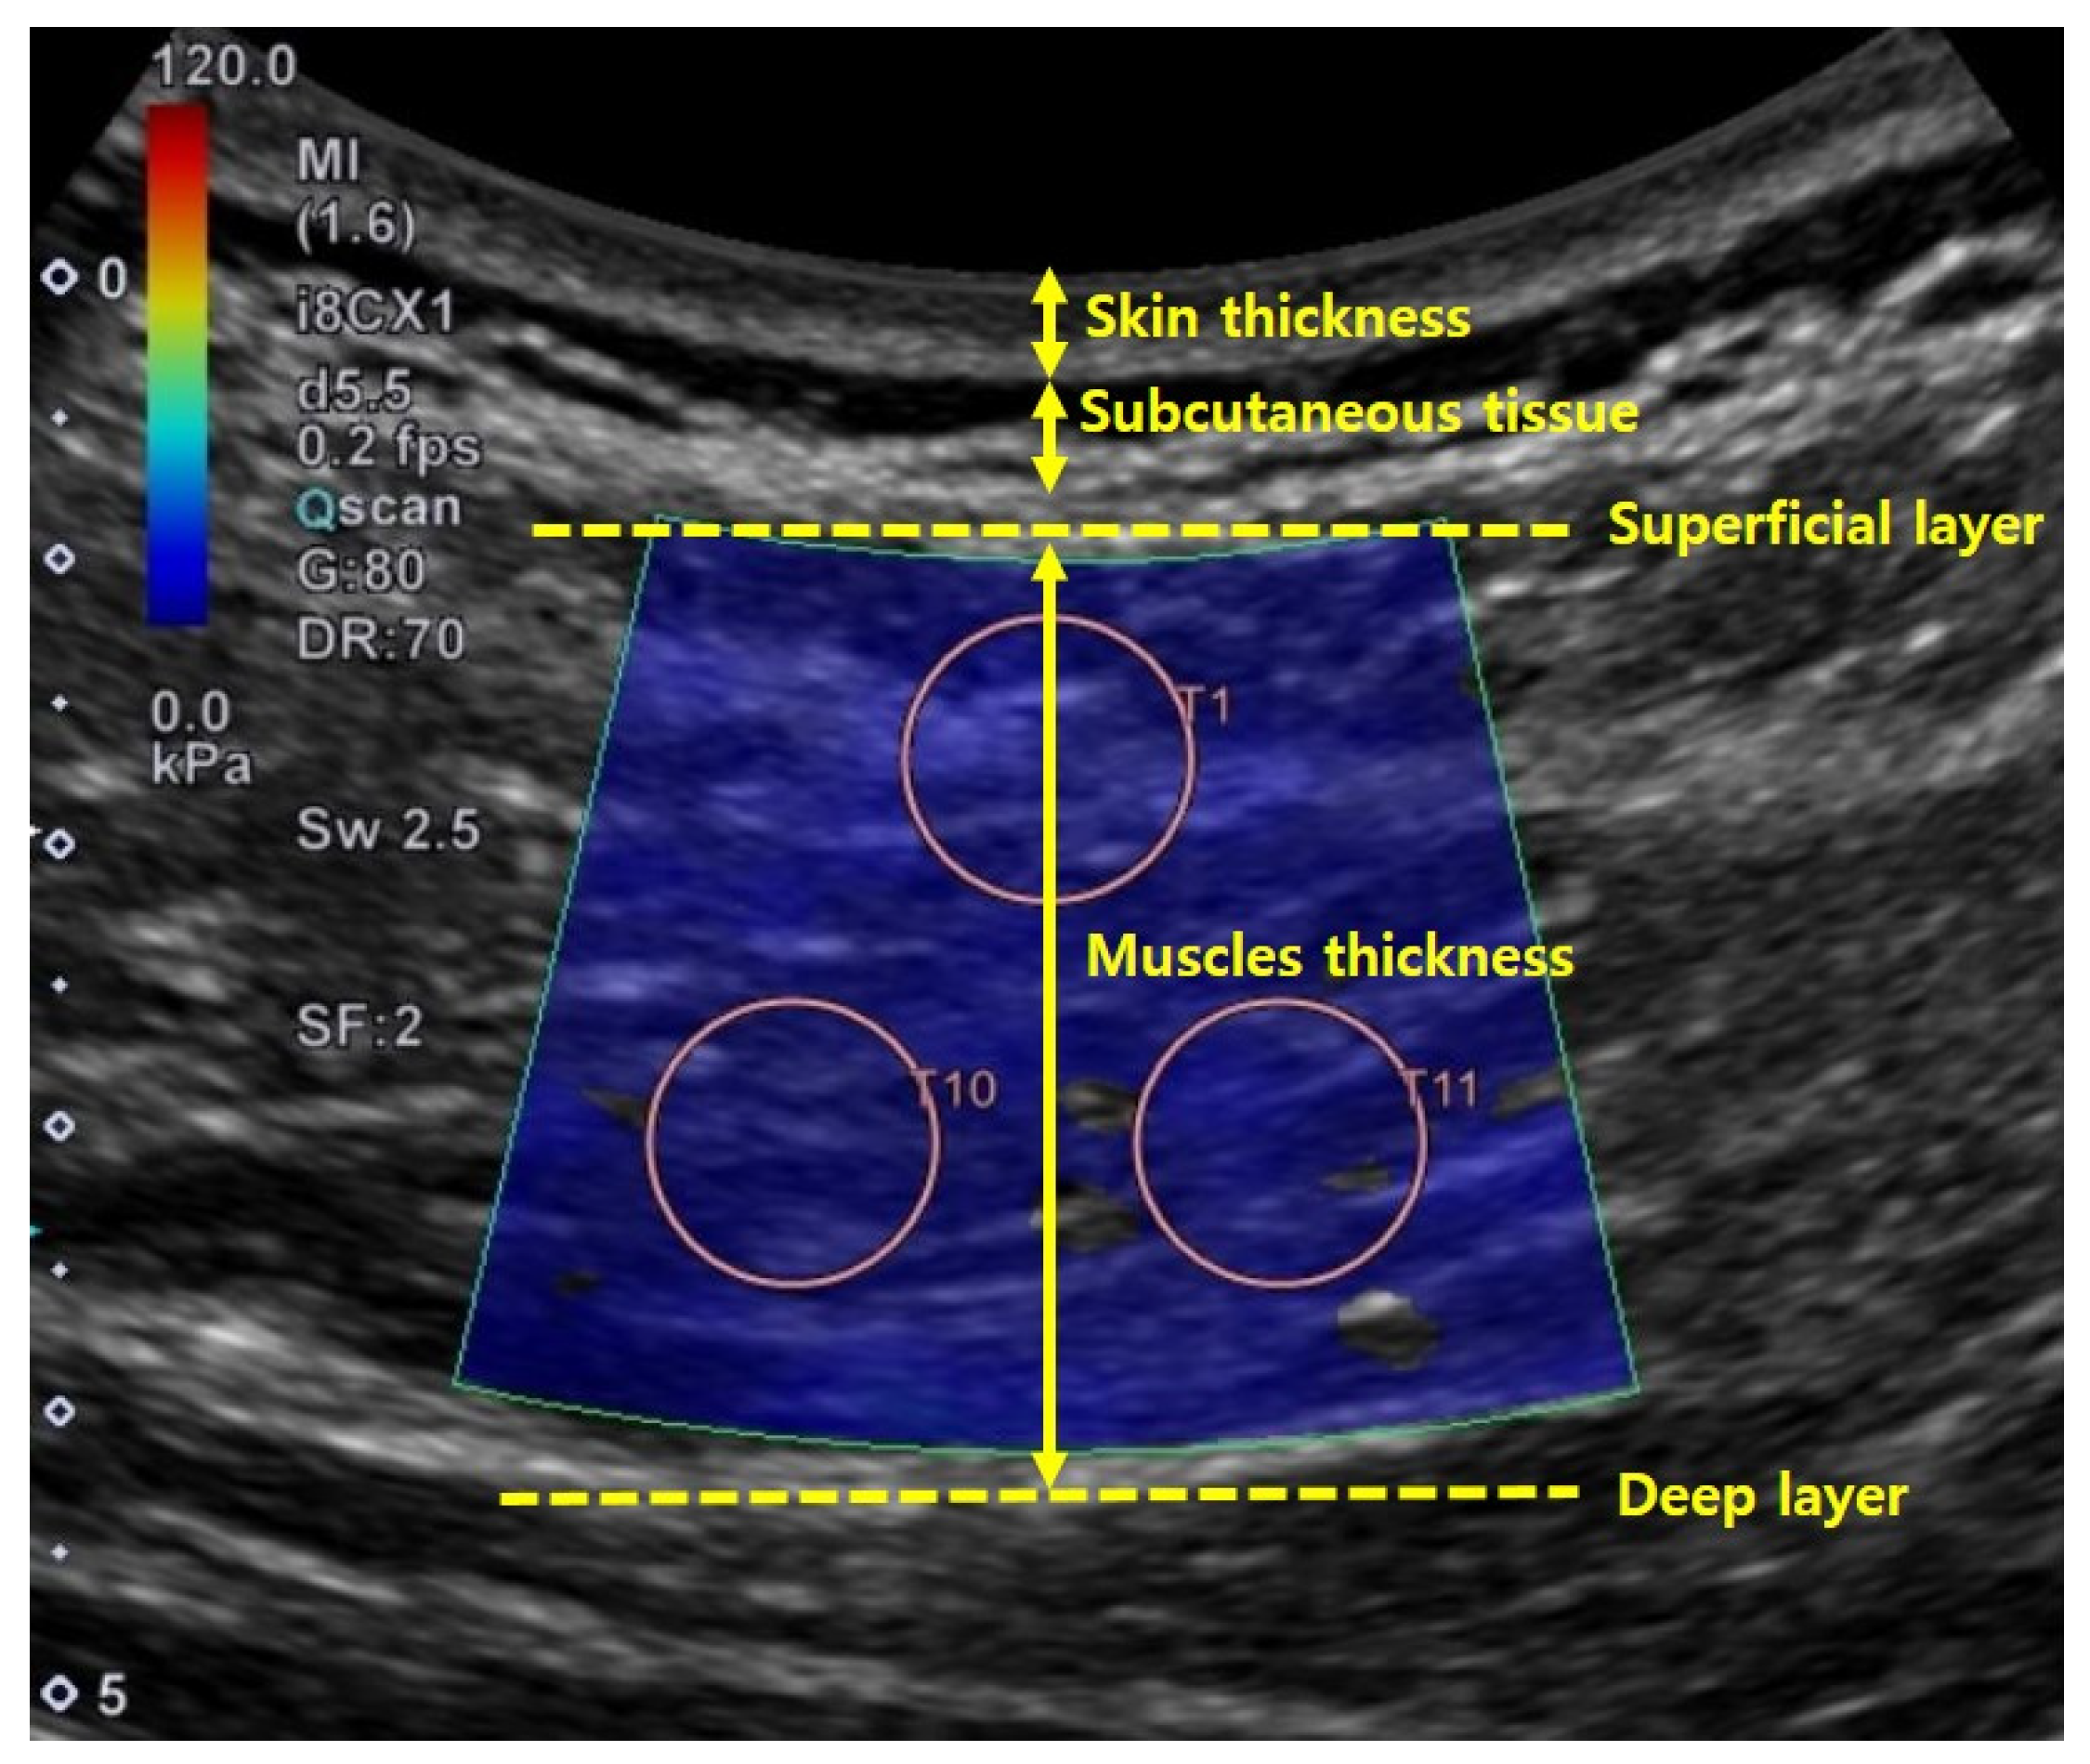

Skin and muscle thicknesses were measured from the collected shear-wave ultrasound images using Image J 1.52a (National Institutes of Health, Bethesda, U.S.). Skin thickness was measured as the distance (cm) between the surface of the epidermis and the subcutaneous tissue. Muscle thickness was measured as the distance between superficial and deep muscle facias. Both skin and muscle thicknesses were measured by drawing a straight line through the center of the image [26] (Figure 4). Skin and muscle thicknesses were measured using one shear-wave ultrasound image per muscle and condition.

Figure 4.

Method used to determine skin and muscle thicknesses in ultrasound image.